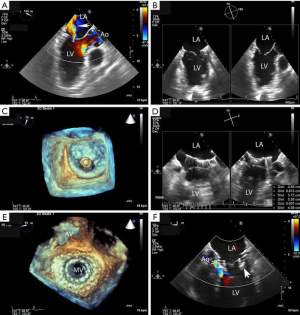

Patients with symptomatic primary or secondary MR may be considered for TMVR with the IntrepidTM system. All patients undergo contrast-enhanced, cardiac computed tomography (CT) of the mitral valve annulus to determine suitability and choice of the prosthesis size (6,7). In general, a prosthesis size is chosen that will allow 10% to 30% oversizing in the mitral annular perimeter, inter-commissural diameter and septal-lateral diameter, while minimizing risk of LVOT obstruction. While there are no set boundaries for neo-LVOT area, a predicted value of >1.3 cm2 is typically used. The cardiac CT scan is used to determine the access site for the thoracotomy and the location for placement of the sheath in the left ventricle. Patients are placed under general anesthesia for the procedure, with guidance by transesophageal echocardiography (TEE) and fluoroscopy (Figure 2). A small left thoracotomy is performed, followed by placement of left ventricular apical purse string sutures. A 6 or 7 French (Fr) vascular sheath is introduced into the left ventricle over a wire, followed by exchange for the IntrepidTM delivery catheter. The IntrepidTM catheter is directed to the left atrium with the assistance of TEE and centered in the mitral valve orifice. The atrial brim is expanded using hydraulic delivery, then aligned on the mitral annulus with care to maintain the brim in the left atrium. The IntrepidTM valve is deployed during a short run of rapid ventricular pacing. The delivery catheter is then withdrawn from the left ventricle and the apical access site is closed. In general, patients are hospitalized in the intensive care unit for 24 to 48 hours, followed by transfer to telemetry. Patients are placed on warfarin with international normalized ratio (INR) target range of 2.5 to 3.5 for three months, as well as a single antiplatelet agent, consisting of either aspirin (75, 81, or 100 mg daily) or clopidogrel (75 mg daily).